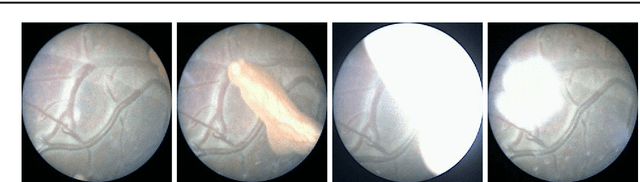

Purpose: The standard clinical treatment of Twin-to-Twin Transfusion Syndrome consists in the photo-coagulation of undesired anastomoses located on the placenta which are responsible to a blood transfer between the two twins. While being the standard of care procedure, fetoscopy suffers from a limited field-of-view of the placenta resulting in missed anastomoses. To facilitate the task of the clinician, building a global map of the placenta providing a larger overview of the vascular network is highly desired. Methods: To overcome the challenging visual conditions inherent to in vivo sequences (low contrast, obstructions or presence of artifacts, among others), we propose the following contributions: (i) robust pairwise registration is achieved by aligning the orientation of the image gradients, and (ii) difficulties regarding long-range consistency (e.g. due to the presence of outliers) is tackled via a bag-of-word strategy, which identifies overlapping frames of the sequence to be registered regardless of their respective location in time. Results: In addition to visual difficulties, in vivo sequences are characterised by the intrinsic absence of gold standard. We present mosaics motivating qualitatively our methodological choices and demonstrating their promising aspect. We also demonstrate semi-quantitatively, via visual inspection of registration results, the efficacy of our registration approach in comparison to two standard baselines. Conclusion: This paper proposes the first approach for the construction of mosaics of placenta in in vivo fetoscopy sequences. Robustness to visual challenges during registration and long-range temporal consistency are proposed, offering first positive results on in vivo data for which standard mosaicking techniques are not applicable.